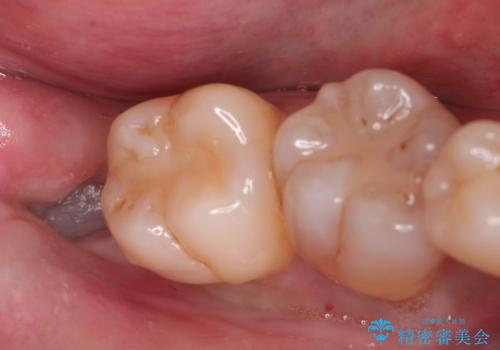

金属の詰め物がはずれた。

保険で治療した歯が欠けた。オールセラミッククラウンによる修復

担当医 河口智英